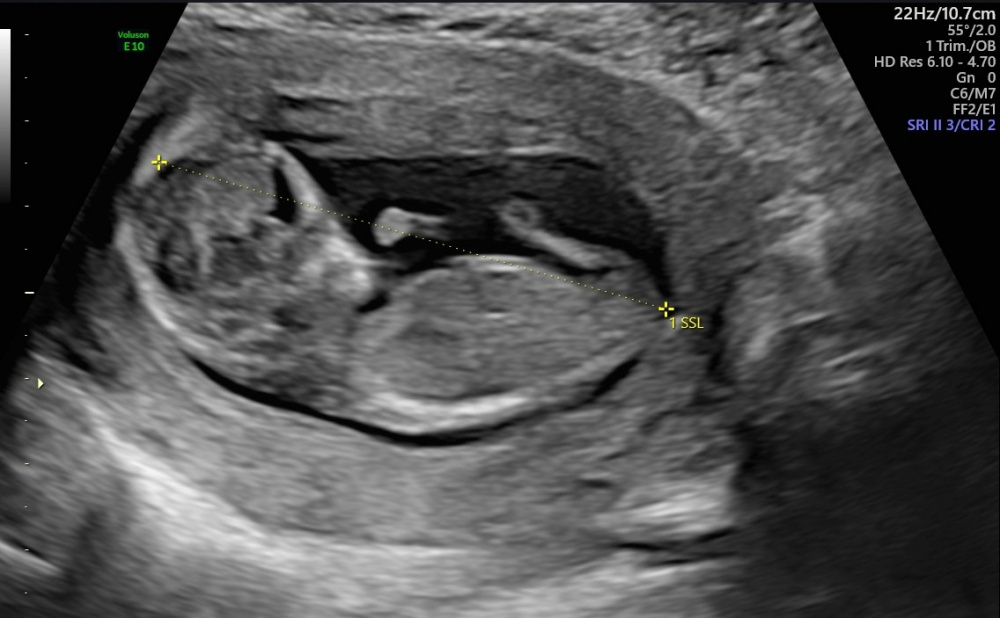

Hallo meine Lieben, waren heute beim Ultraschall SSW17

Das Geschlecht spielt bei uns keine Rolle, da wir bereits einen Jungen und ein Mädchen haben.

Aber aus reiner Neugier, was meint ihr anhand der Bilder, Mädchen oder Junge